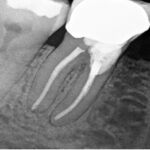

- October 14th – Resorption repairs were done on teeth #27, #29, and #30

- December 21st – A follow-up scan showed that the molar was still doing well, and the bicuspids looked healthy

- December 27th – Endodontic treatment (root canal) was performed on tooth #19, along with surgical repairs on teeth #19, #20, and #22

We used a full-mouth scan to monitor this case. While this gave us a broad view, it doesn’t provide the same fine detail as a limited field of view scan. There were some artifacts (image distortions) from previous repairs on the right side, but the left side images were clearer.